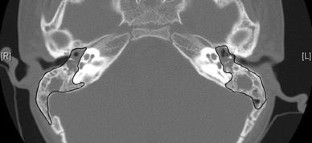

Pneumatic otoscopy is most helpful for optimally assessing the presence of a middle ear effusion (MEE). To evaluate the diagnostic usefulness and to obtain objective parameters of video pneumatic otoscope (VPO) in ears with MEE, we measured the minimal and maximal pressures in the external auditory canal and recorded the movement of the tympanic membrane (TM) during VPO in 28 ears with MEE and 13 healthy ears. The movements of the TM at static stage, positive and negative pressure stages of VPO were analyzed in terms of the position of the umbo and the angle and length of the malleus. The percent volume of air space out of the total tympanomastoid air cell system (the air index) was obtained from the temporal bone CT, and was used as a reference standard. As a result, minimal pressure and the movement of the umbo from negative pressure stage in ears with MEE were significantly different from the normal ears. The minimal pressure, maximal pressure and the movement of umbo from negative pressure to static stage were significantly correlated with the air index. These results may suggest useful parameters for quantitative analysis of VPO for the visual diagnosis of MEE.

Fig 3